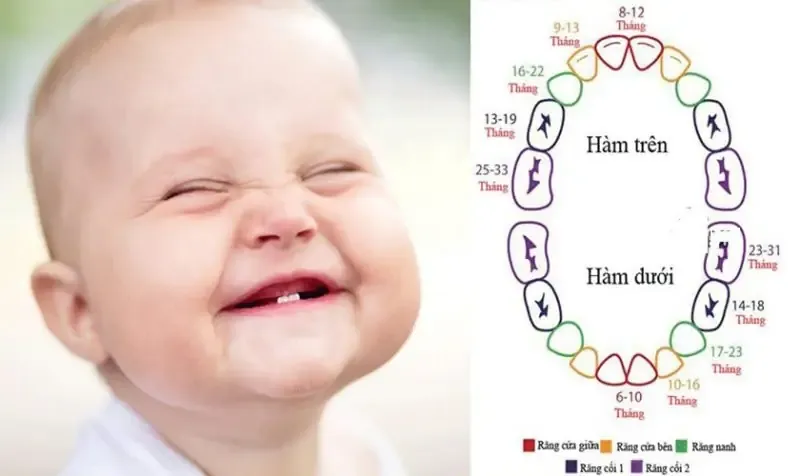

Răng ở trẻ nhỏ là một phần quan trọng trong hệ tiêu hóa và sức khỏe tổng thể của con người. Việc hiểu rõ về cấu trúc,